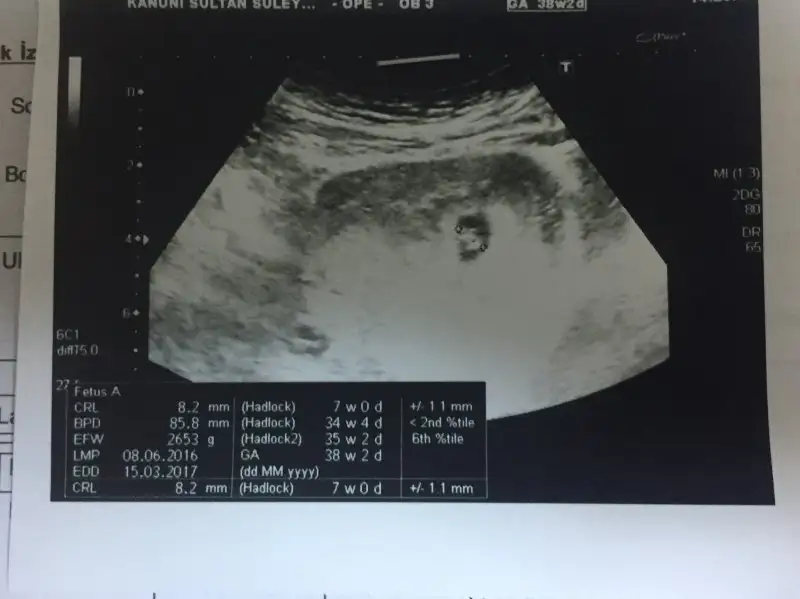

Merhabalar 11+1 deyim karindan usg sizce ne olabilir=) oncelikle saglikli hayirli evlatlar olsun ama insan merak etmeden duramiyor.=)

7+3 lük karından ultrason görüntüm bu şekildedir. Hem kesenin şekline hem de bebişin duruşuna göre yorum yaparsanız sevinirim. Tşk.